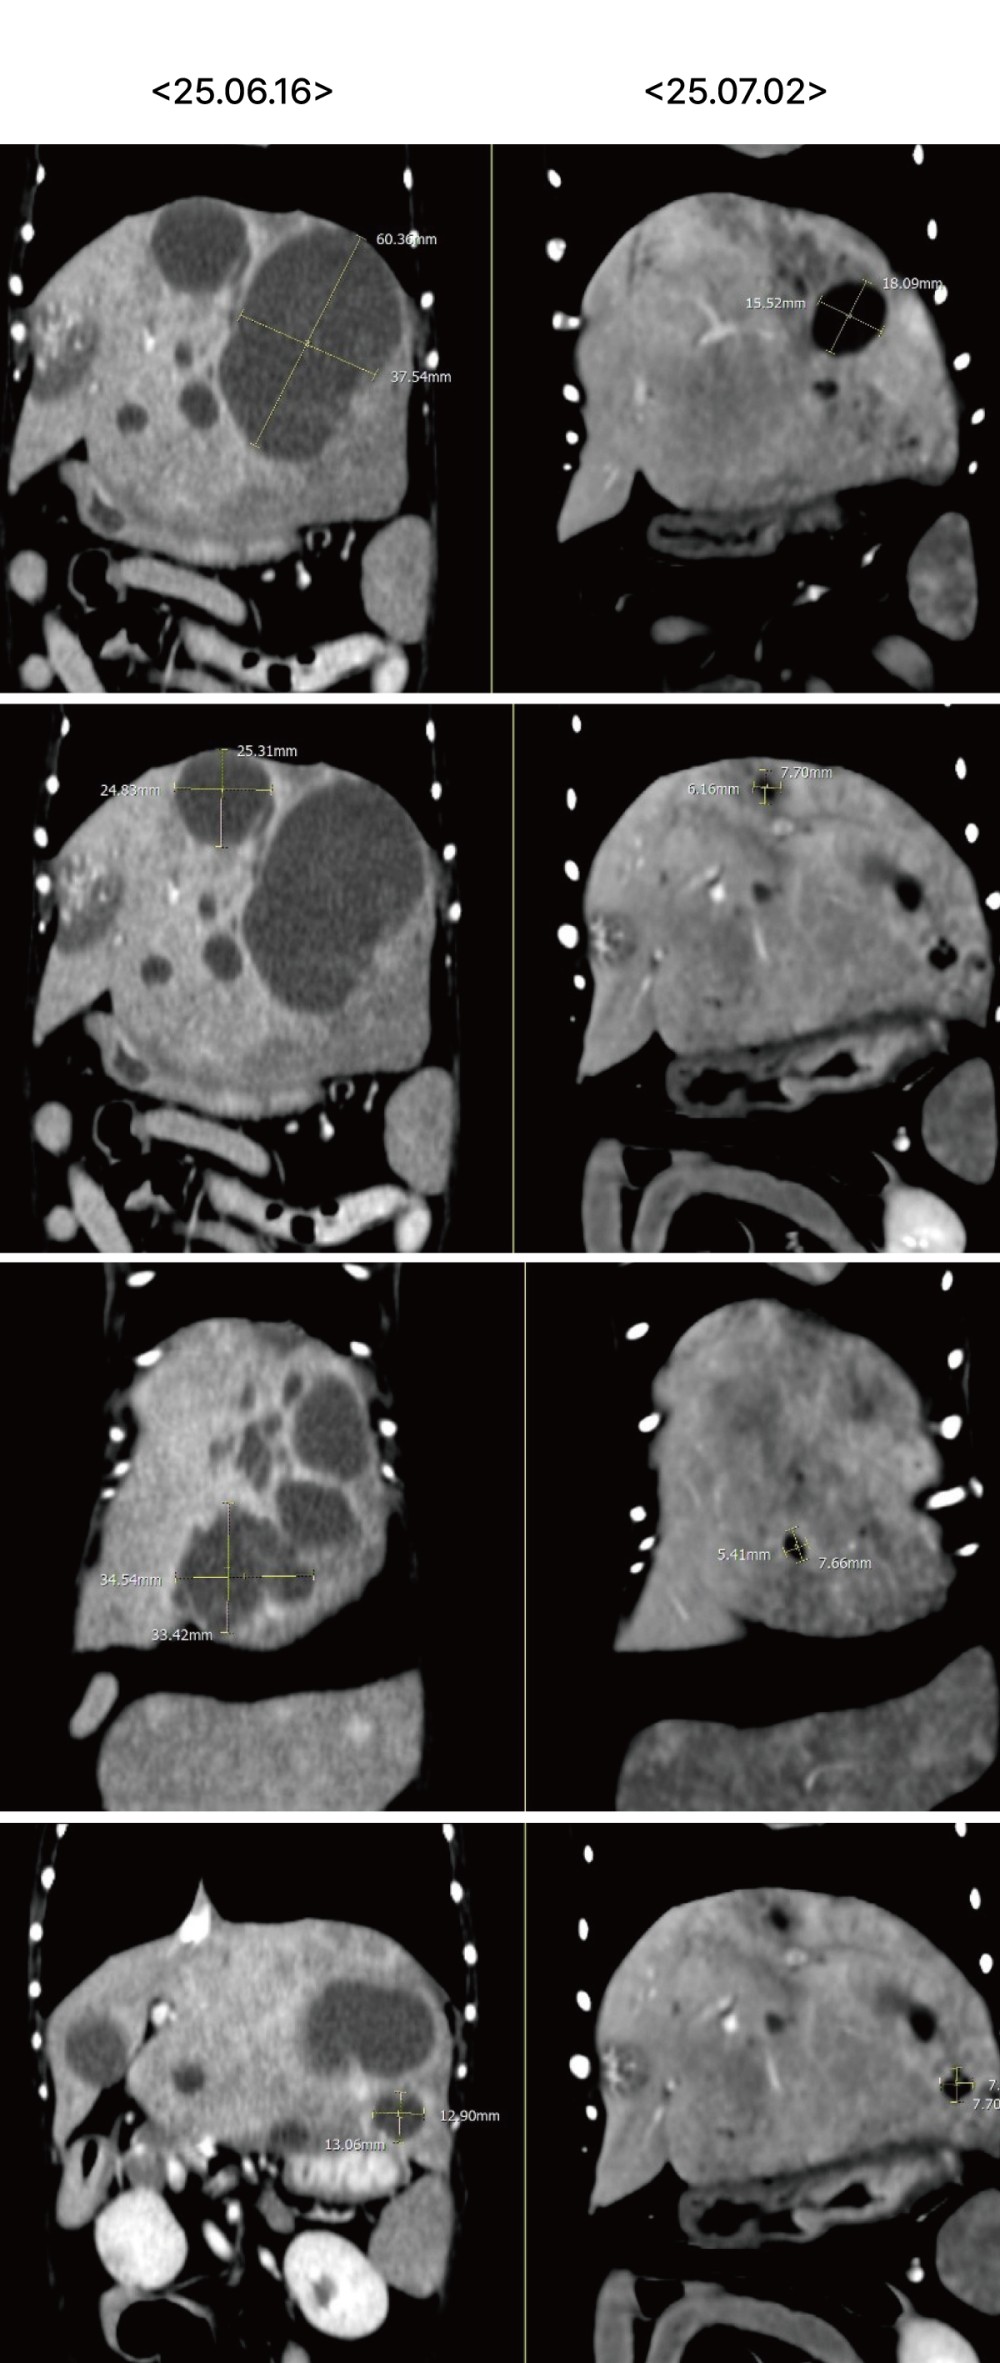

추가로 CT를 시행하였으며, 그 결과 간 실질 내 다발성 낭성 병변과 함께 췌장 석회화, 총담관 확장, 담석이 확인되었습니다.

실제로 추적 CT에서도 간 내 낭성 병변의 크기가 뚜렷하게 감소하고 림프절 크기 또한 감소하여 처치에 대한 반응이 명확하게 확인되었습니다 .

▲ 좌측 내측엽과 가측엽에 위치하던 cystic lesion의 크기 뚜렷한 감소 및 불규칙한 변연으로 변화

▲ 이전 검사에서 뚜렷하게 종대되어 관찰되었던 간 림프절 크기 감소